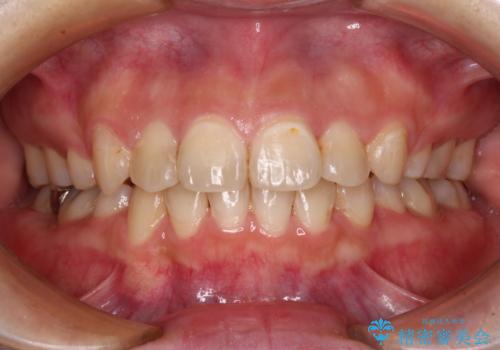

デコボコとディープバイトを治したい インビザラインによる矯正治療

前歯のがたつき 深い噛み合わせを改善したい